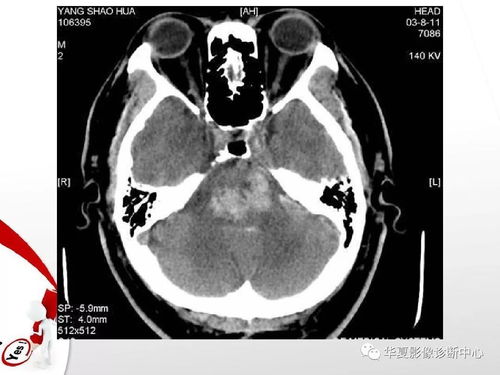

冠状动脉粥样硬化引发的血管狭窄是冠心病的一个明显信号。当血管的狭窄程度超过一半,即超过50%时,我们通常会诊断为冠心病。其他因素如血管炎、先天性畸形等导致的血管狭窄则不属于冠心病的范畴。

诊断心脏病的过程是一个综合评估的过程。轻度的血管狭窄可能只是由于老化、高血压等非冠心病因素引起。我们需要结合具体的症状(如心绞痛)以及专业的检查(如冠脉造影)来进行综合判断。一些特殊情况如肌桥等发育异常导致的血管狭窄,也不能简单地归为冠心病。

除了冠状动脉的血管狭窄,其他部位的血管狭窄,如颈动脉狭窄,可能会间接对心脏造成压力。但这类情况并不直接属于心脏病的范畴。